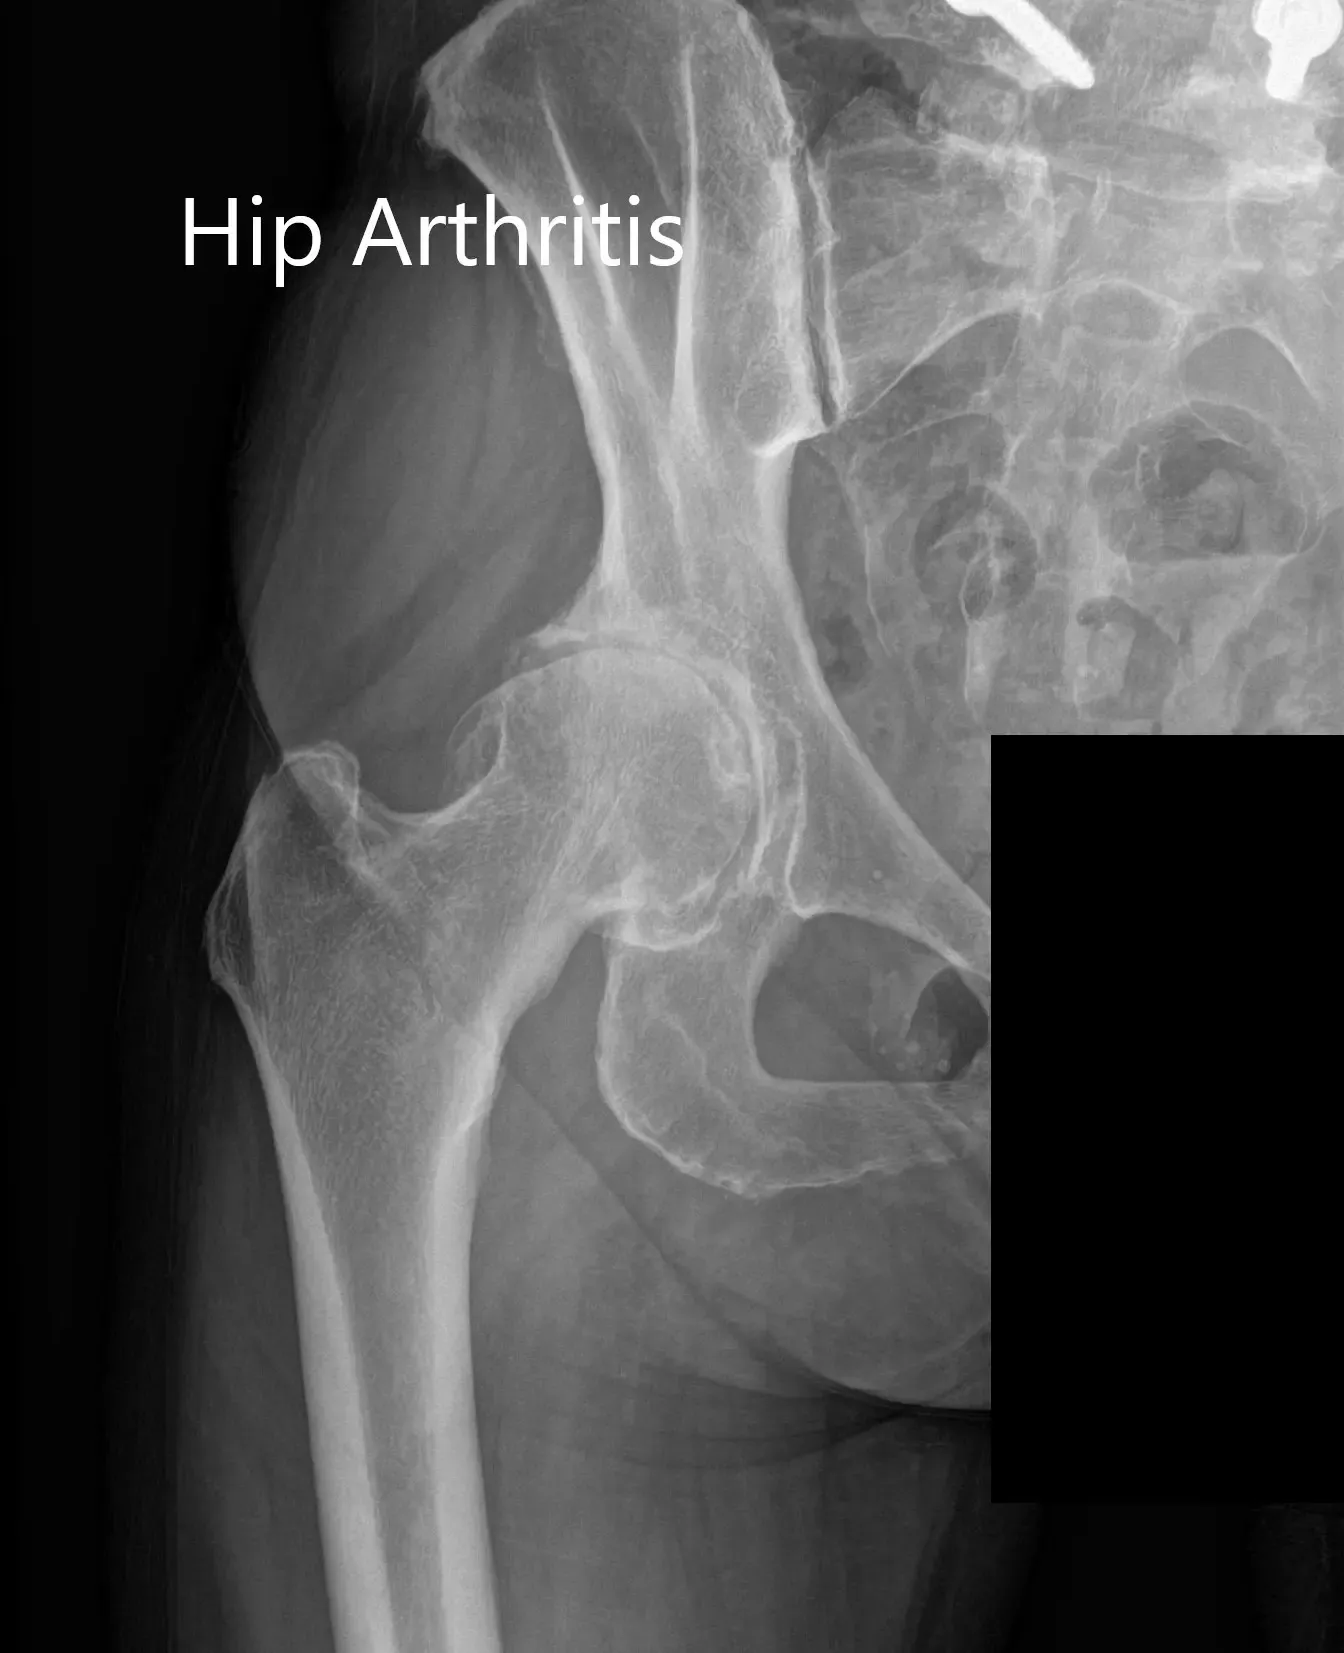

Imaging revealed osteoarthritis of the right hip with joint space reduction and osteophytes. The patient was advised right total hip robotic replacement. The risks, benefits, and alternatives were discussed with the patient at length and she agreed with the plan.

Preoperative X-ray Showing the AP and lateral views of the right hip.